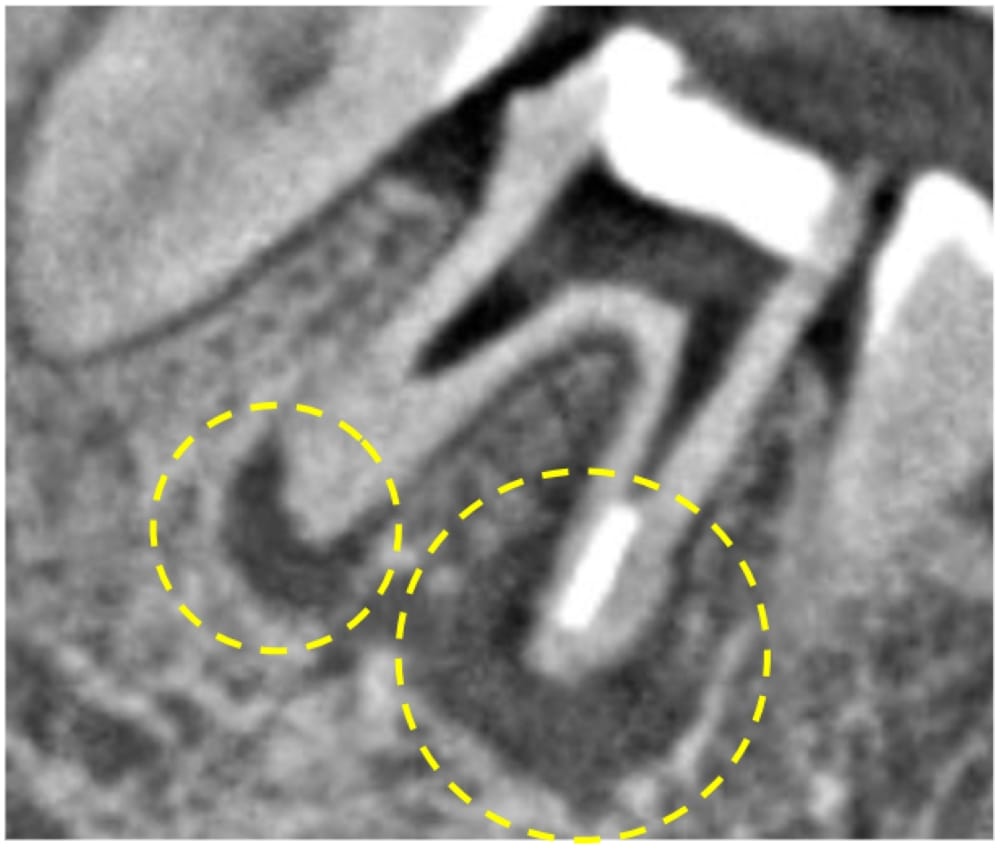

根管治療から6ヶ月が経過し、普段の痛みは消失したとのことでした。この時点では噛み合わせても上の歯と当たらないように高さを落としている状態ですが、食べ物が当たると強く響くのが心配とのことなので、追加で6ヶ月(術後12ヶ月まで)経過観察となりました。

12ヶ月後の経過観察

12ヶ月経過時には、日常生活でほとんど気にならないレベルにまで症状は軽減しました(たまに違和感を感じる程度)。患者様にも、おそらくこれ以上感覚は戻らないことをお伝えしたところ、問題ないとのことで、仮歯装着後、最終補綴(クラウン)へ移行しました。